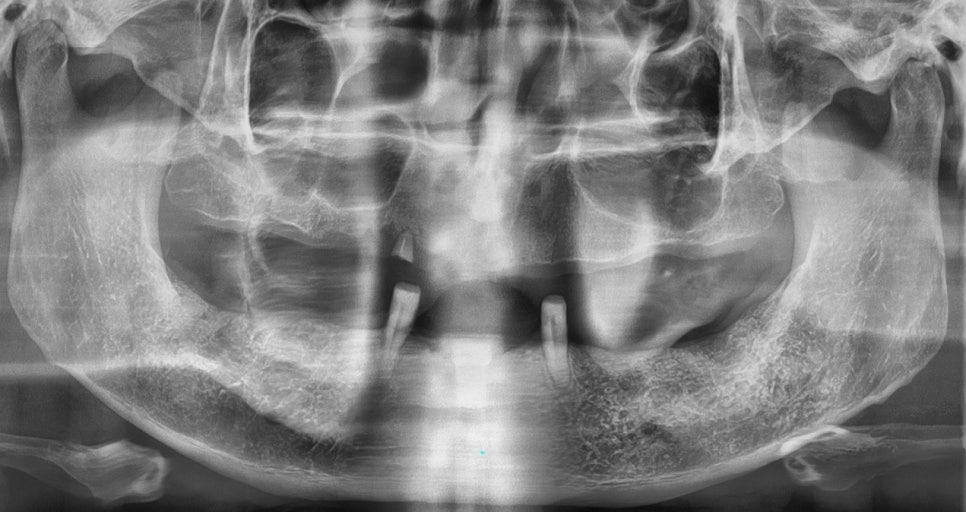

현재 상태를 파악하기 위해서

우선 3D CT와 x-ray를 통해서

구강 구조물과 상태를 확인하는 과정을 거쳤습니다.

CT와 X-ray를 통해서 상악 구치부에 있는

잔존 치조골의 높이와

필요한 뼈이식의 양을 먼저 파악했습니다.